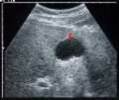

Hepatic Candidiasis

TARGET LESION

Caused by FUNGUS

HIV CHEMO

Fever localized pain

SONO

hypoechoic mass with echogenic center “TARGER LESION”

shows diffuse, homogeneous, hypoechoic foci